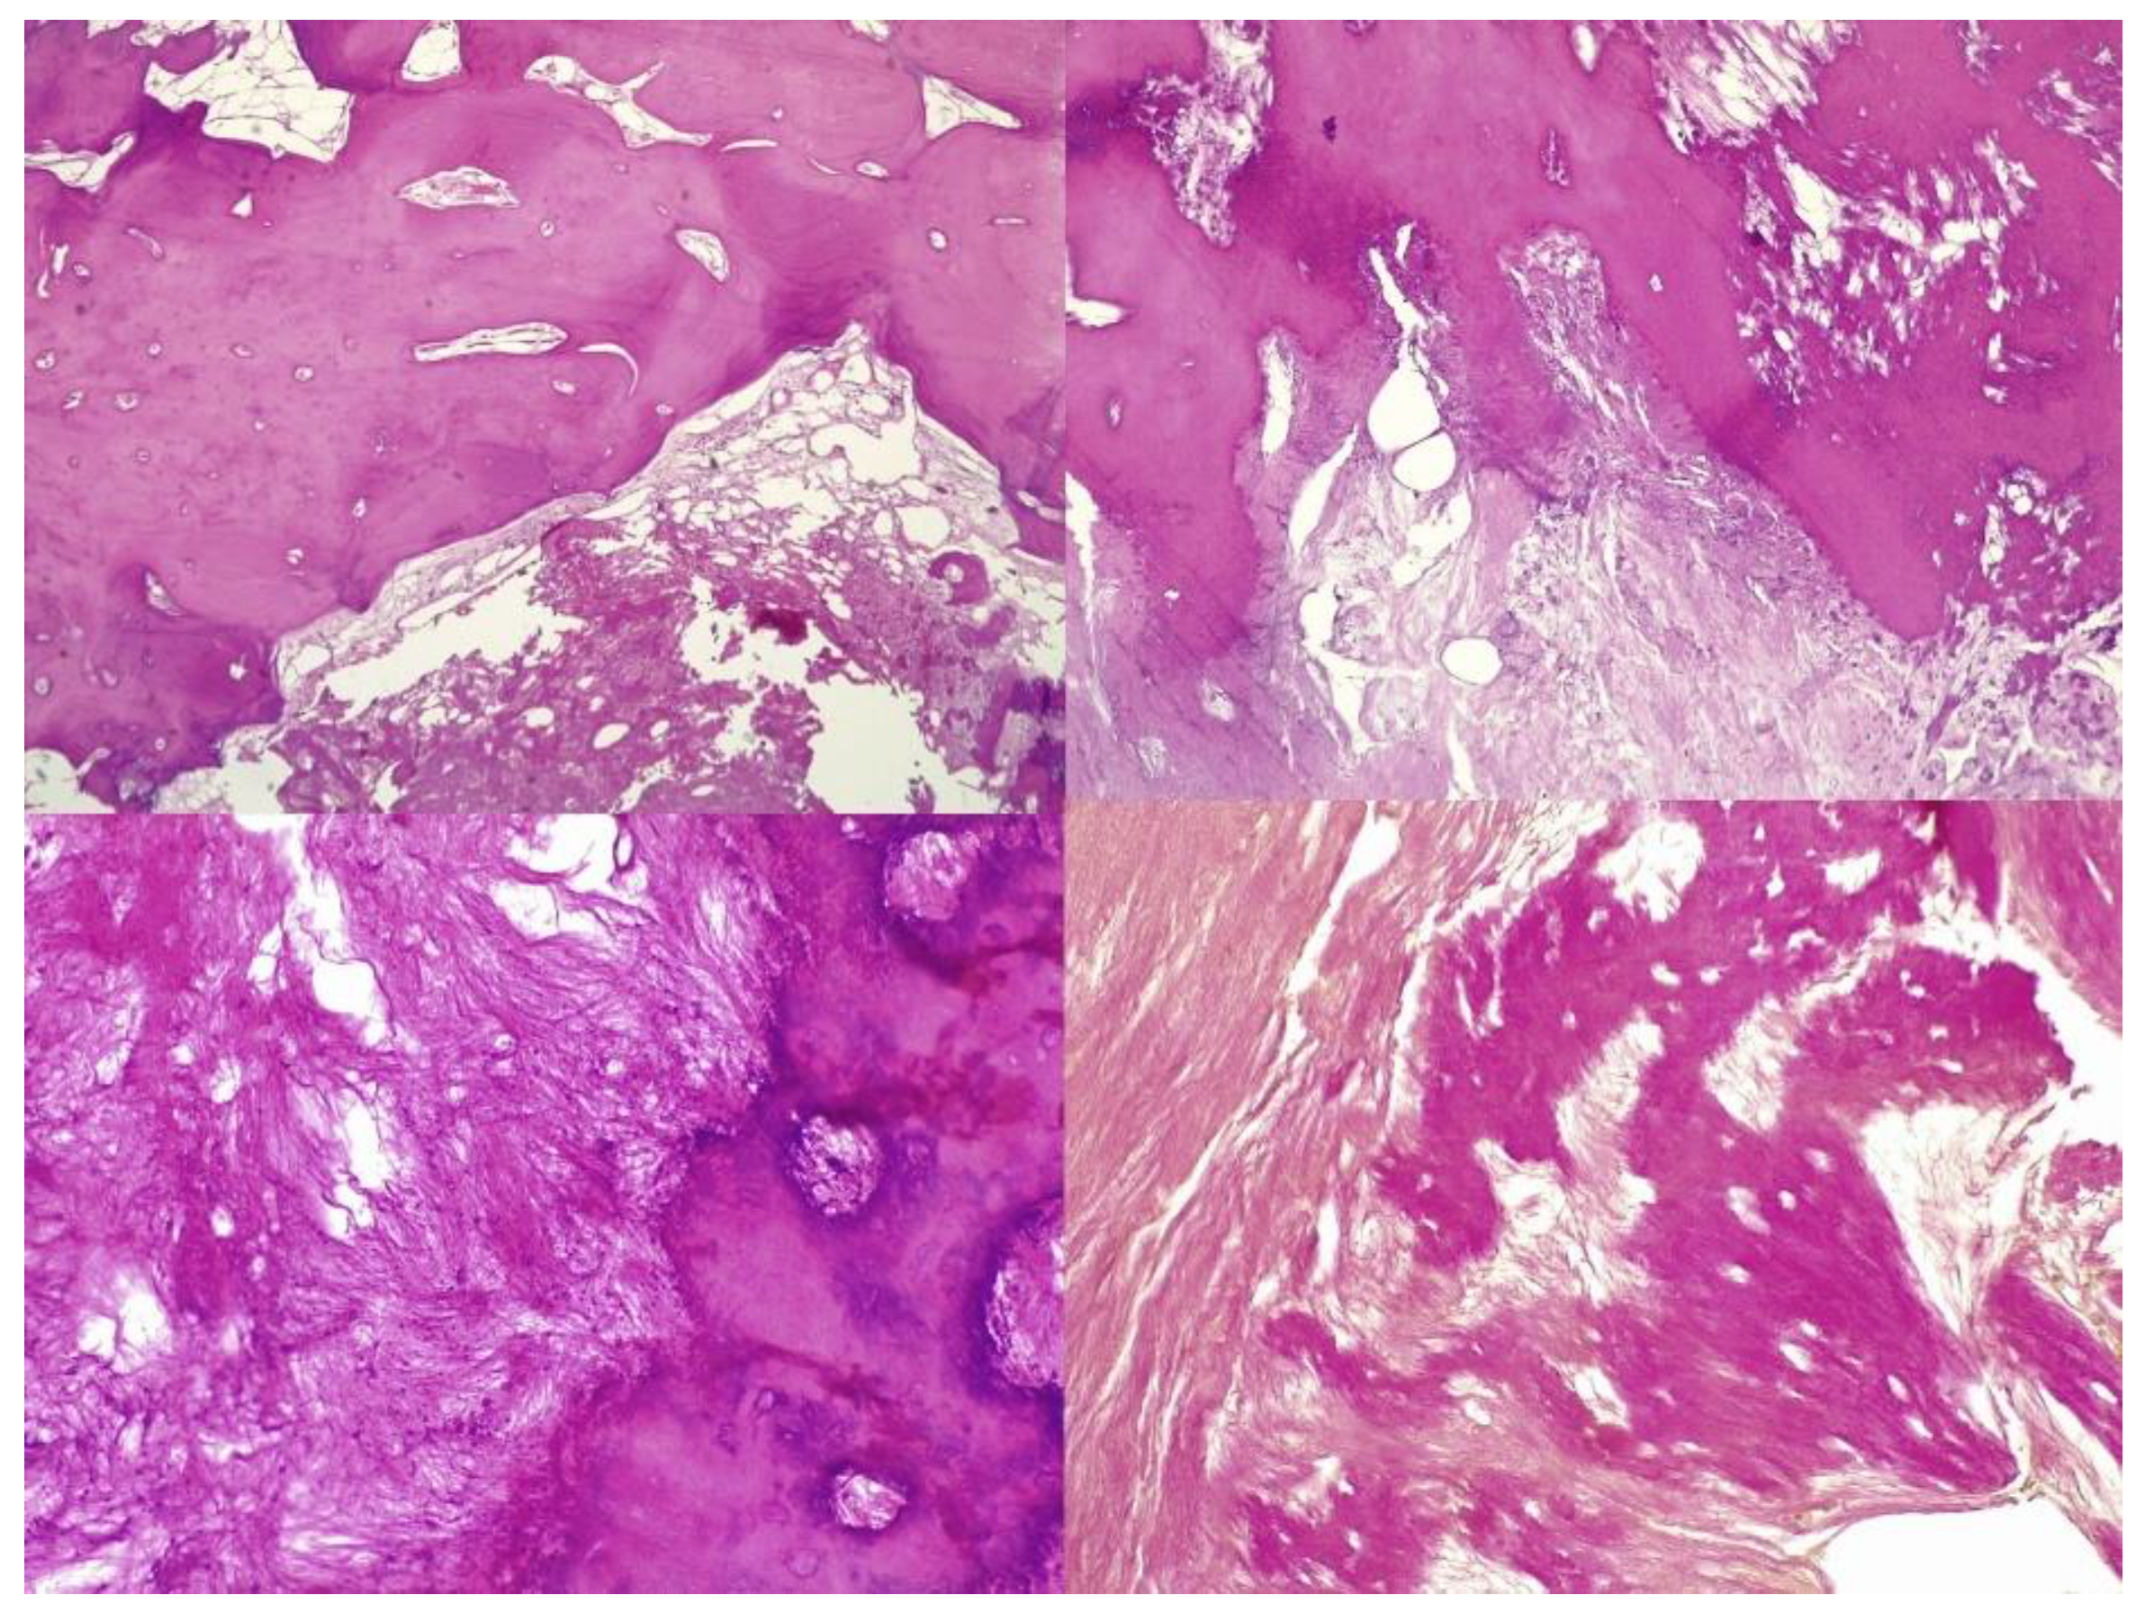

We present the case of a 46-year-old female patient who presented to the orthopedics and traumatology department of the University Emergency Hospital of Bucharest with severe pain in the left thigh and limitation of joint mobility. Following the clinical examination, the patient complained of pain in the middle third of the left thigh in the antero-medial part; the pain appeared spontaneously and was aggravated during physical activity. The pain started about two years ago, but the patient experienced complete pain relief after the administration of non-steroidal anti-inflammatory drugs. In the last six months, the patient presented an increase in pain intensity without significant improvement following the administration of non-steroidal anti-inflammatory drugs. The patient used non-steroidal anti-inflammatory drugs daily, without a significant improvement in pain, which significantly affected her quality of life. No shortening of the limbs or stiffness in the adjacent joints was observed. At the local examination, the patient had normal skin, without local changes, without inflammatory signs present, and no signs of ischemia. An X-ray of the femur in the antero-posterior and lateral incidence was performed which identified a unique bone lesion with dimensions of approximately 12/10 cm in the coronal plane located on the antero-medial cortex of the femur with a mixed appearance (Figure 1 and Figure 2). After that, we performed a whole-body scintigraphy which highlighted the same bone lesion described in the radiological examination with moderate uptake in the late phase, without highlighting other associated bone lesions.

Figure 1. Full-leg X-ray in the antero-posterior view showing a sclerotic bone lesion (12 cm) associated with lytic areas with thickening of the bone cortex.

Figure 2. Lateral view X-ray of the femur showing sclerotic bone associated with lytic areas with thickening of the bone cortex.